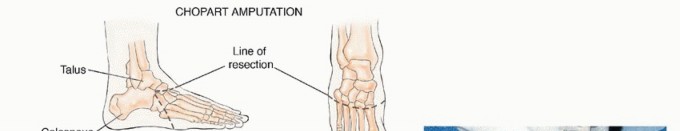

* أنواع البتر في القدم:

* البتر عبر الكاحل (Ankle Disarticulation/Syme Amputation): إزالة القدم عند مفصل الكاحل. يسمح هذا النوع بتحمل الوزن على طرف الكاحل المتبقي ويوفر قاعدة جيدة للطرف الصناعي.

* البتر تحت الركبة (Transtibial Amputation): في حالات الأورام الأكثر انتشارًا، قد يكون من الضروري بتر الساق تحت الركبة. يركز الدكتور هطيف على الحفاظ على أكبر قدر ممكن من الساق لتمكين استخدام الأطراف الصناعية المتقدمة.

* النهج الحديث في البتر: يستخدم الدكتور هطيف أحدث التقنيات لضمان بتر نظيف، وتقليل المضاعفات، وتهيئة الطرف المتبقي بشكل مثالي لتركيب الأطراف الصناعية.